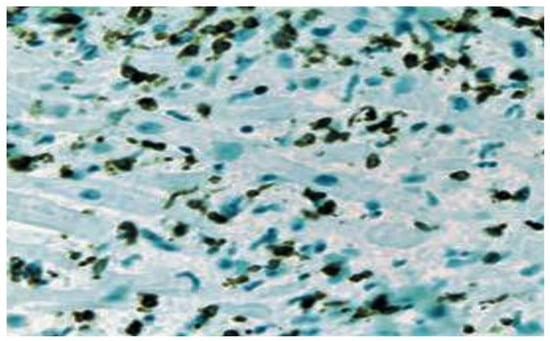

- Basso, C.; Leone, O.; Rizzo, S.; De Gaspari, M.; Van Der Wal, A.C.; Aubry, M.-C.; Bois, M.C.; Lin, P.T.; Maleszewski, J.J.; Stone, J.R. Pathological features of COVID-19-associated myocardial injury: A multicentre cardiovascular pathology study. Eur. Heart J. 2020, 41, 3827–3835. [Google Scholar] [CrossRef]